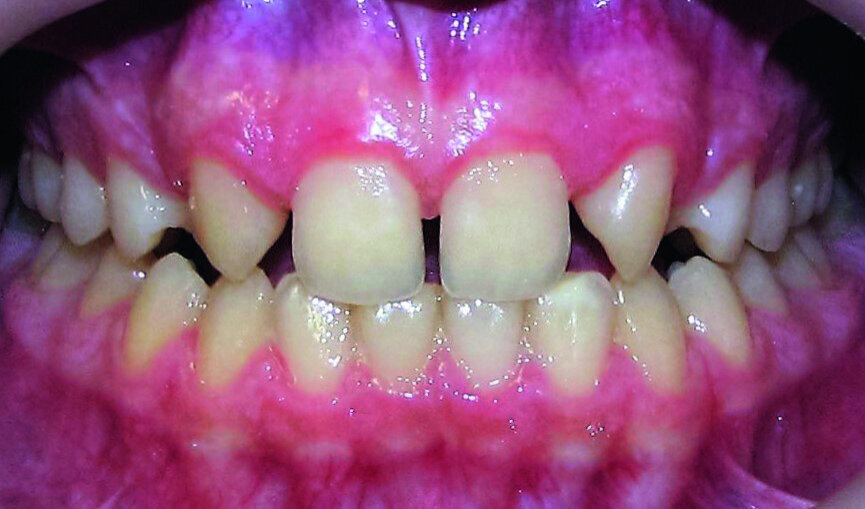

Then occlusal analysis (Figs. 11–21) was performed:

- Skeletal Class III (Fig. 17).

- Dental Class I.

- Maxillary hypoplasia with lower arch dental compensations.

- Insuficient overbite and overjet.

- Upper spacing due to the laterals agenesis (Fig. 18).

- Upper midline deviated to the right.

A 13-year-old patient complaining about the aesthetic aspect of her smile was sent to my office by a general dentist with a diagnosis of the bilateral lateral incisors agenesis.